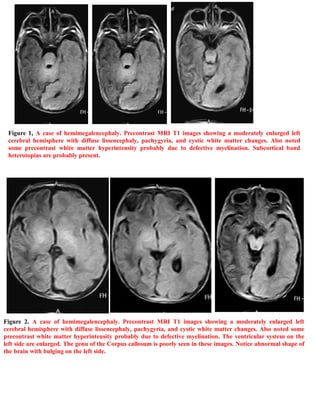

Download to read offline